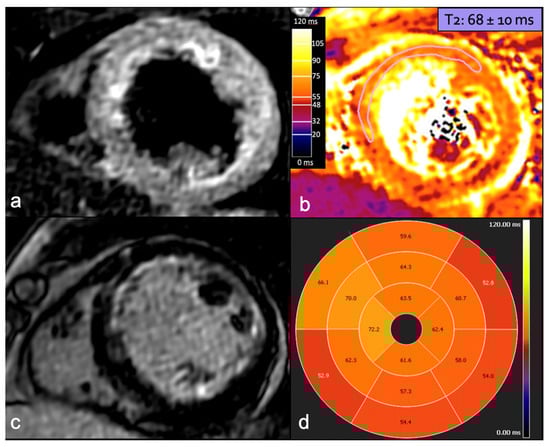

Figure 7.

A 38-year-old woman presented with chest oppression and hypertension eight days after delivery. TTE (a) showed decreased LVEF (45%) and global left ventricle hypokinesia. CMR confirmed left ventricle disfunction, but no focal delayed enhancement was identified on LGE imaging (b) and STIR images (c) showed faint and diffuse hyperintensity. Quantitative mapping showed high global myocardial native T1, ECV, and T2 values ((d–f): mean value of the basal segments shown in the Figures). TTE: transthoracic echocardiogram; LVEF: left ventricular ejection fraction; CMR: cardiac magnetic resonance; LGE: late gadolinium enhancement; STIR: short tau inversion recovery; and ECV: extracellular volume.

The prevalence of myocardial edema—detected by high signal intensity on T2w images and increased T1 and T2 mapping values—varies in the literature. It is more common in the acute phase of PPCM and may indicate a potentially reversible myocardial injury. Persistent myocardial edema is associated with an increased risk of developing poor left ventricular function recovery [105]. To the best of our knowledge, only two studies have analyzed native T1 mapping, T2 mapping, and extracellular volume (ECV) values in PPCM, with partially consistent findings. Liang et al. found an increase in all three values in PPCM patients compared to healthy controls. They also found that baseline values were higher in unrecovered patients than in recovered ones, suggesting a potential prognostic role for these markers in PPCM [109]. LGE detection is fundamental to assess prognosis and functional recovery in PPCM patients as its presence is associated with a poor prognosis, correlating with worsening ventricular function over time or lack of functional recovery [105,107,110]. The prevalence of LGE in PPCM patients varies widely across studies, ranging from 5% [111] to 71% [107], with variability likely due to differences in cohort size, racial and genetic factors, and timing of assessments. Supporting the hypothesis of the time dependence of detection of tissue composition alteration, LGE was more likely to be present in follow-up scans in comparison to acute-phase scans [105]. When identified, LGE typically exhibits a non-ischemic pattern, with a linear or patchy distribution, primarily localizing in subepicardial and intramural areas [112]. The localization of LGE in the left ventricle is also variable, with a prevalence in the basal- and mid-ventricular antero-septal regions [107,112]. Finally, CMR is useful in the detection of intracardiac thrombi, a relatively common complication in PPCM [113]. The suggested CMR protocol for patients with PPCM is shown in Table 3, with the administration of GBCAs reserved for the postpartum period [94].